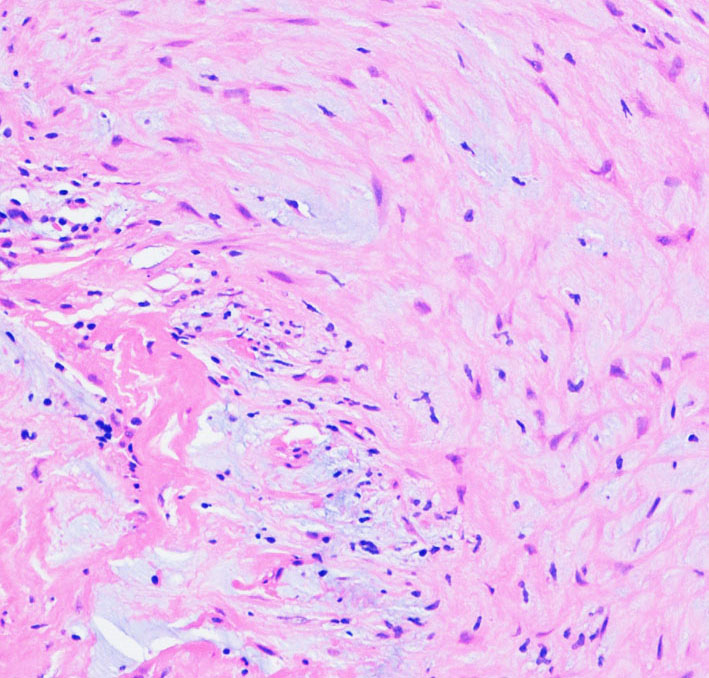

病理所見では,幼児型のpilomyxoid astrocytomaの部分が混在します。その部分が増殖と腫瘍増大に関わっています。T2強調画像で高信号でガドリニウム増強される部分です。

myxoidな部分です。右下のMIB-1染色では3%ほどの陽性率であり,数年単位では腫瘍増大があり得ることを示します。柔らかく出血性で吸引摘出できる部分の腫瘍です。IDH wild type, BRAFV600 wild type, H3K27 wild type, FGFR1 N546K mutationでした。

厚く肥厚した視神経鞘の内部の視神経組織はほとんど腫瘍に置き換わっていて,GFAPで染色され高度の石灰化を伴います。これは腫瘍というよりも瘢痕化してしまった,adult-type pilocytic astrocytomaに認められる所見です。

Rosenthal fiber, eosinophyric granular body, psammoma bodyなどが認められ,成熟しきって退行変性に移行するpilocytic astrocytomaの像です。この部分は増大しません。線維性に極めて硬い組織です。